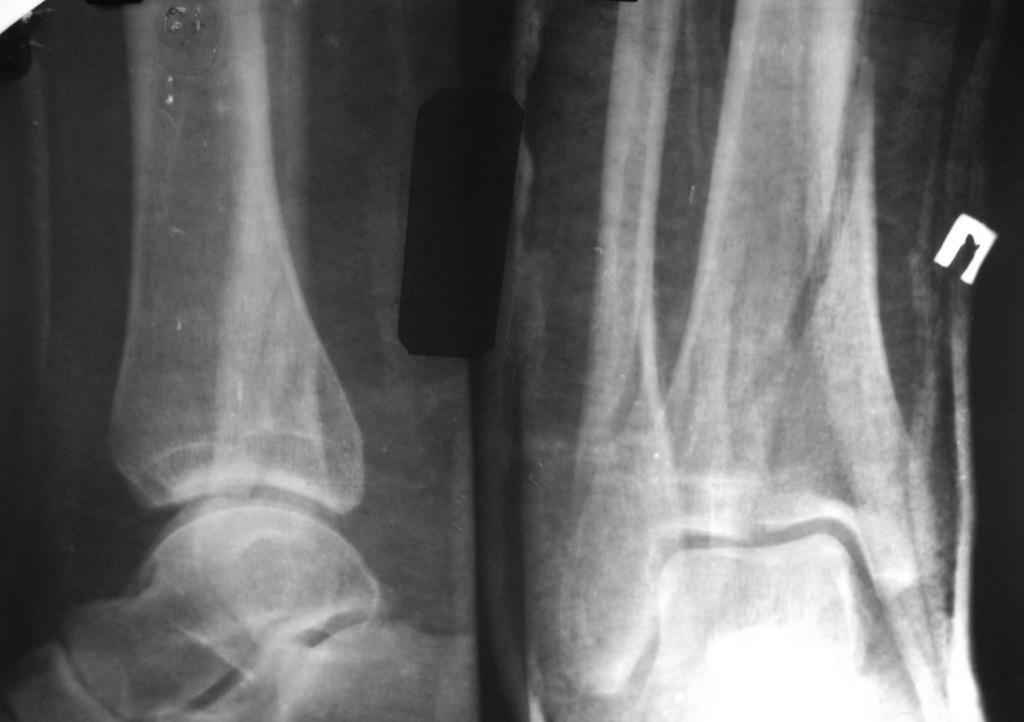

Re: перелом пилона. тактика лечения

прошу прощения за то, что забыл приложить снимки